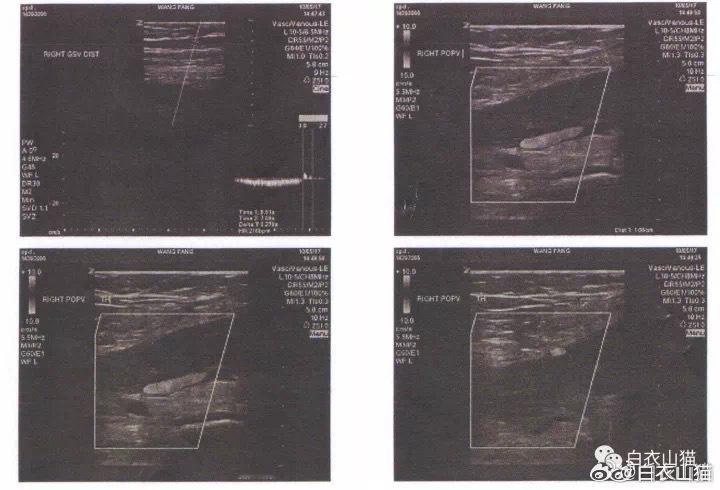

王医生给她查了一个下肢血管的彩超。

图片2:患者腘静脉的血栓形成。

如上图,这一查,就查出了患者的右侧腘静脉有血栓形成。

这个时候,小腿肿胀的原因也找到了,看起来病因也有了,腘静脉还没有完全堵塞,病情也不严重,只要门诊抗凝治疗就可以了。